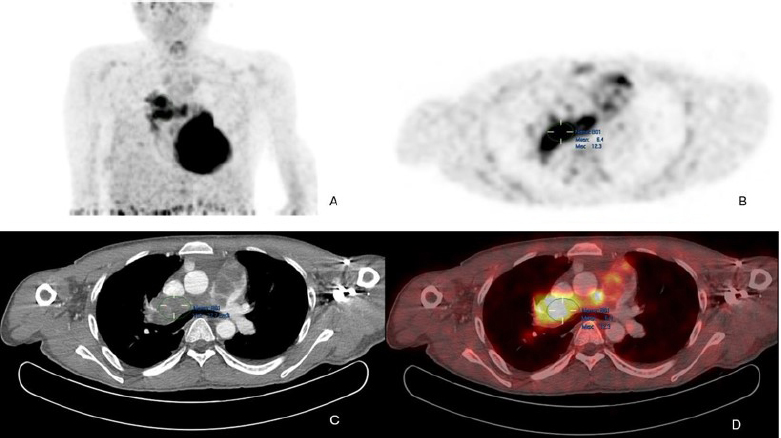

The patient was further investigated with computed tomography (CT), cardiac magnetic resonance imaging (MRI), and positron emission tomography-computed tomography (PET-CT). The CT scan showed a mass extending from the RVOT into the main pulmonary trunk, causing significant stenosis. PET/CT showed a fluorodeoxyglucose (FDG) avid lesion in the right ventricular outflow tract region extending to the right main pulmonary artery and the lobar arteries (Fig. 2A-D). Cardiac MRI showed an enhancing filling defect within the RVOT, main, and right pulmonary arteries, suggestive of a neoplastic process, most probably a pulmonary artery angiosarcoma. Signs of right heart volume and pressure overload were also seen (Fig. 3A-D). The patient also had a right-sided pleural effusion.

(A) Maximum intensity projection (MIP) FDG PET/CT of the thorax demonstrates heterogeneous FDG avidity overlying a branching linear structure in the right side of the mediastinum.

(B) Axial PET image shows an intensely FDG-avid linear lesion in the superior right mediastinum, with a maximum standardized uptake value (SUVmax) of 12.3.

(C) Axial CT pulmonary angiography (CTPA) reveals an expansile filling defect occupying the entire luminal diameter of the main pulmonary artery, extending into its proximal branches.

(D) Axial PET/CT image precisely localizes the heterogeneously hypermetabolic mass to the main pulmonary artery and its proximal branches. Additionally, extraluminal FDG activity is observed, suggesting possible tumoral extension.